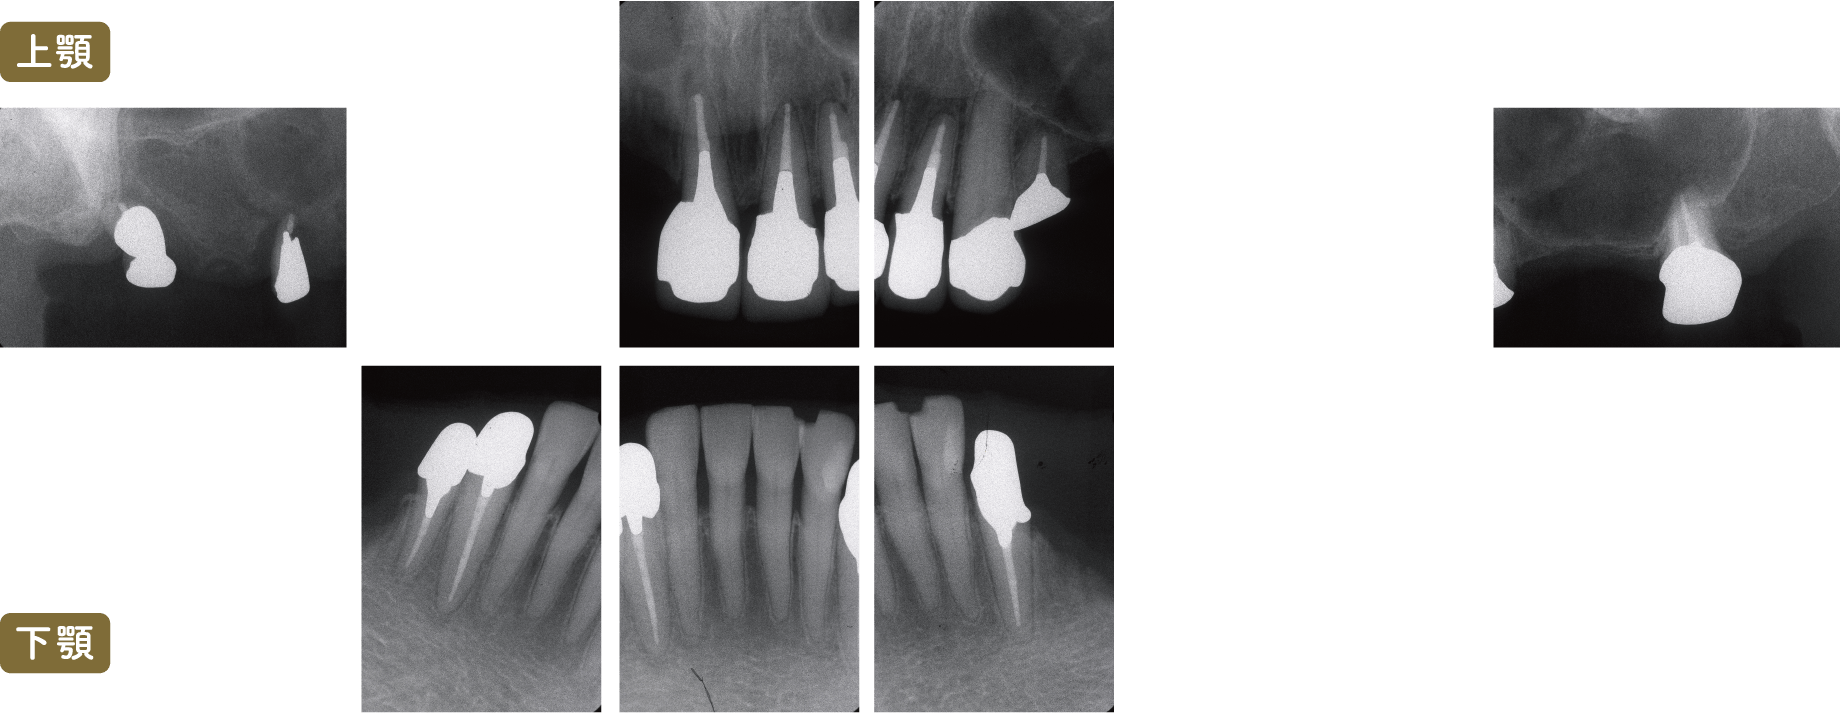

■術前レントゲン写真

上顎の臼歯(奥歯)は歯周病や根の先端が化膿していることから重症であることがわかります

また義歯の支台歯(義歯のバネがかかる歯)にも大きな歯周病が生じています